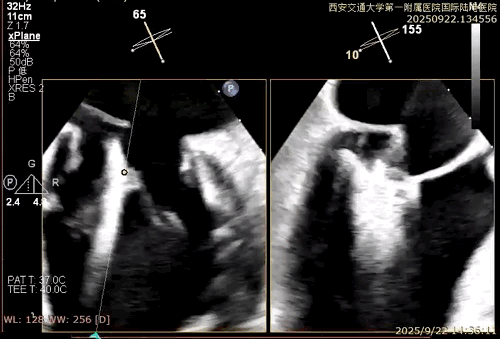

患者男性,69岁,术前TEE评估为FMR患者,因左室功能异常引发二尖瓣重度反流;后叶拴系,反流来源于整个2区,主要集中在2偏1、2偏3。患者瓣口面积约6.2cm²。房间隔可穿刺高度4.5cm。反流束宽度约19mm。AP径36.5mm。

术中在超声引导下完成房间隔穿刺,将第一枚XTR在左房内完成终定位,2偏3区完成植入,夹合效果良好,即刻超声显示轻微反流,完成夹子释放,手术效果良好,手术圆满结束,患者术后6小时即实现床旁活动。